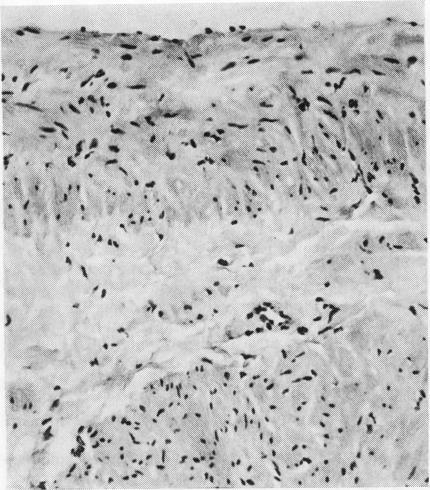

Coexisting congenital primary superior vena caval aneurysm and rheumatic mitral stenosis.

Thorax. 1981 Aug;36(8):638-9. doi: 10.1136/thx.36.8.638.

DOI:10.1136/thx.36.8.638

PMID:7314039